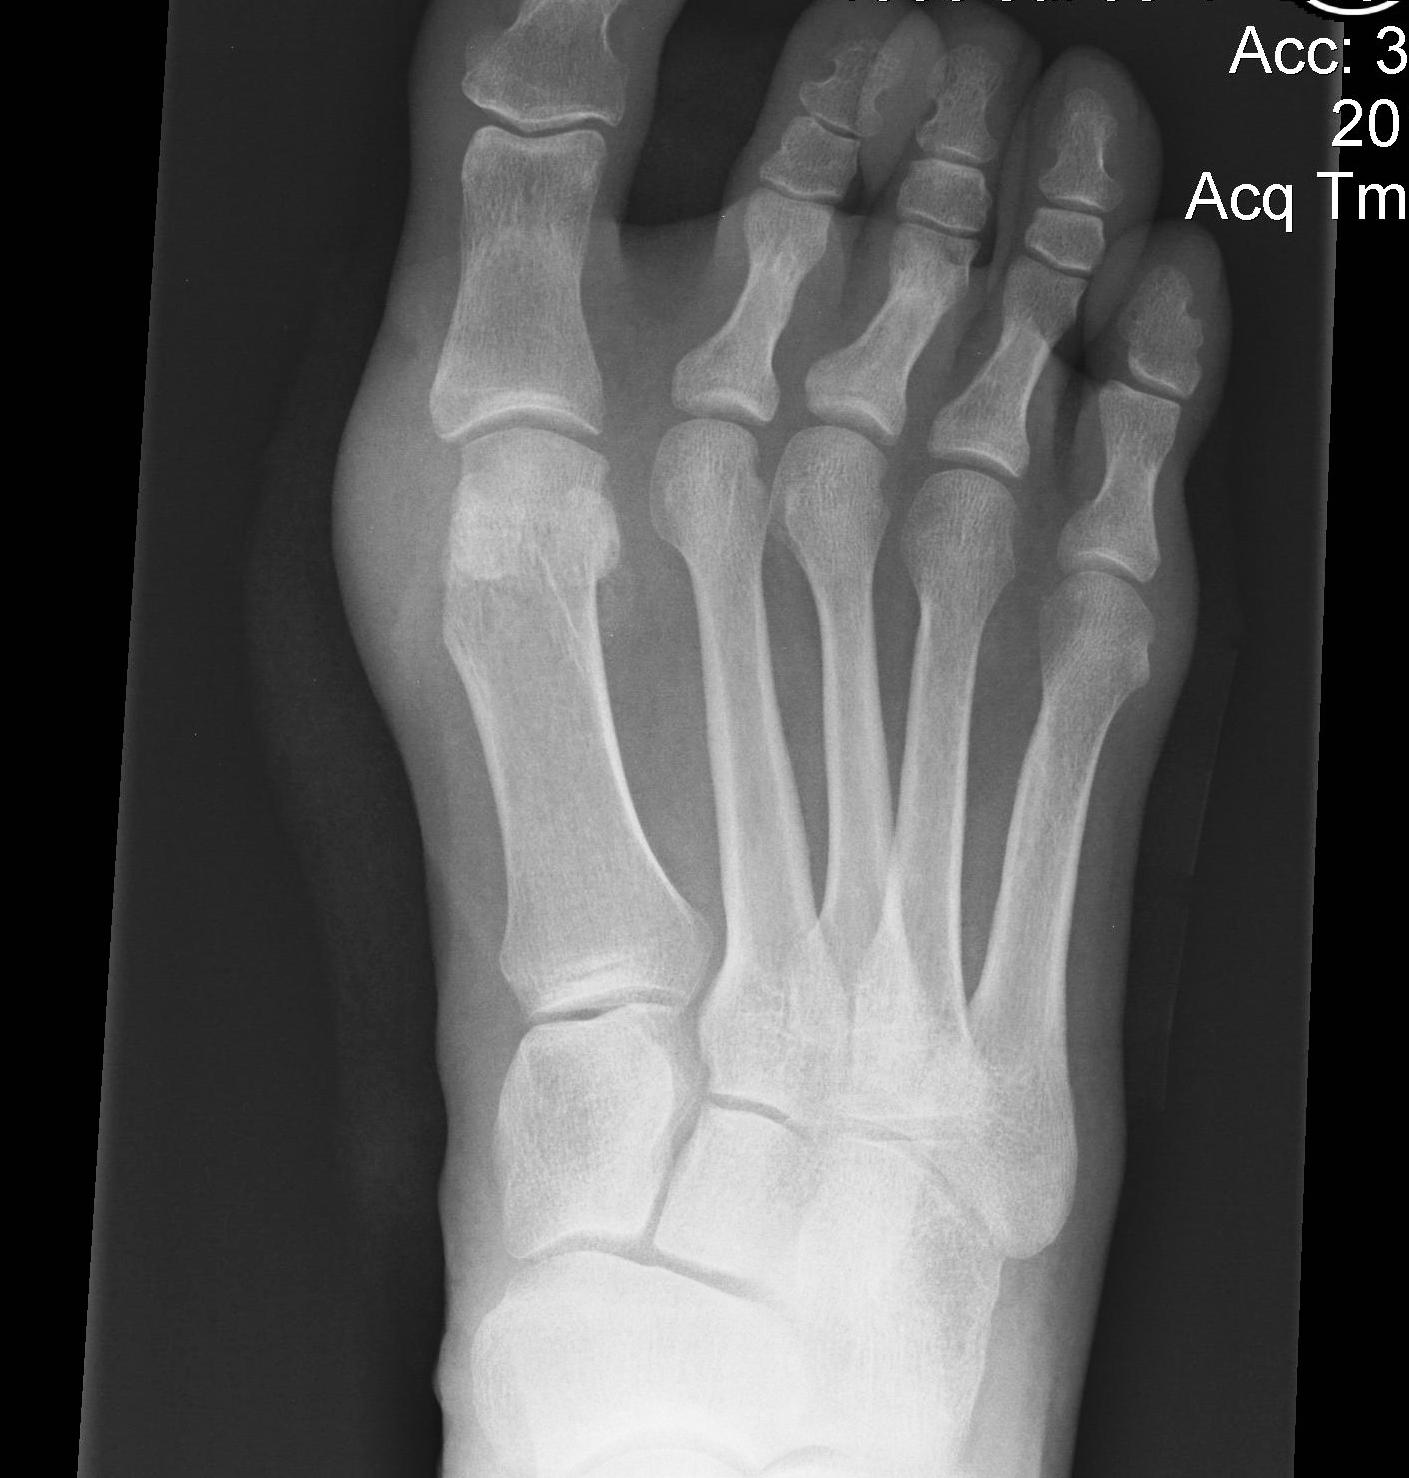

1. Correction of the hallux valgus and intermetarsal angles

2. Creation of a congruent MTP joint

3. Sesamoid realignment

4. Removal of the medial eminence

Chevron osteotomy +/- DSTP

Indications

- incongruent joint

- mild hallux valgus: HVA < 30o / IMA < 15o